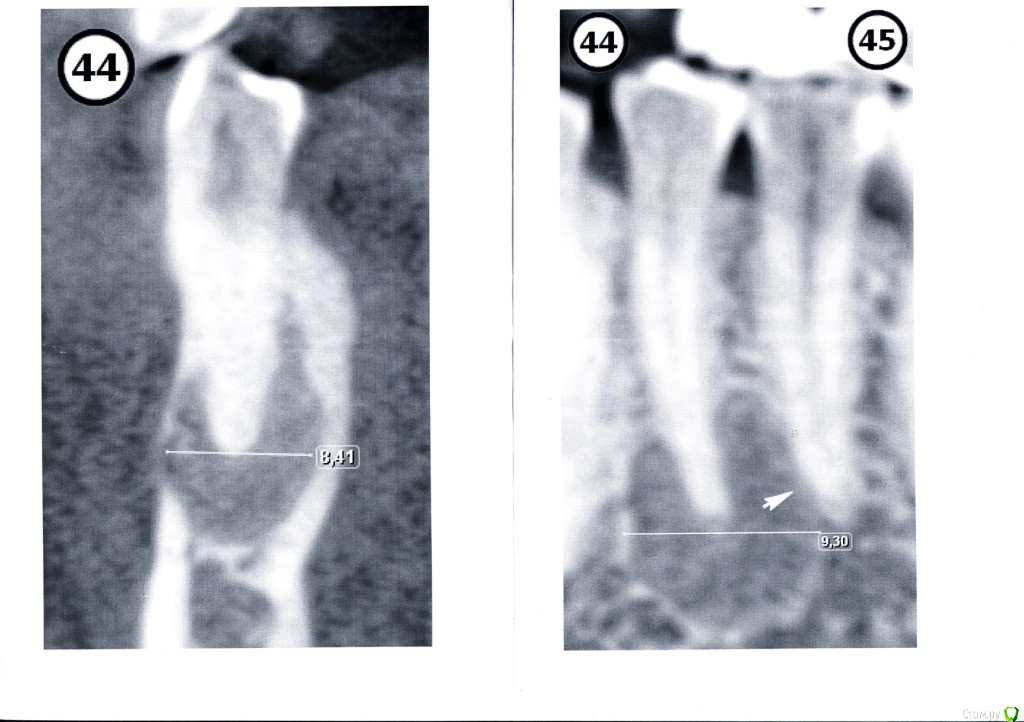

good customer Опубликовано 6 июля, 2016 Поделиться Опубликовано 6 июля, 2016 Здравствуйте, уважаемые Врачи! В мае 2016г на панорамном снимке была обнаружена киста четверки (не болит, не лечили, не били).В июне была сделана кт (в др клинике), где подтвердили кисту зуба. Врач порекомендовал наблюдать в течение 6 мес.Я усомнилась.Сегодня вновь посетила первую клинику и сделали кт. Киста подтвердилась, но не зуба.Как я поняла, киста в тканях проросла так далеко, что истончилась кость и скоро будет задет нерв.Очень благодарна терапевту, что не стал вскрывать зуб, а хирург выписал направление на консультацию в МГМСУ на Вучетича. Успела в институт дозвониться в конце рабочего дня- сказали, что запись на август и положили трубку.Скорее всего, на форуме есть чл-хирурги.Уважаемые Врачи, посмотрите, пожалуйста, мои снимки.Панорамный снимок и отсканированную распечатку фрагмента зуба кт (есть полная версия на диске).Подскажите, пожалуйста, кому из врачей в данном институте можно довериться (или в др лечебном заведении)?Спасибо. Ссылка на комментарий

good customer Опубликовано 10 июля, 2016 Автор Поделиться Опубликовано 10 июля, 2016 Добрый вечер, уважаемые Врачи! Нашла панорамный снимок от 2014г. кисты, вроде, не было.... Ссылка на комментарий

Alejandro Опубликовано 12 июля, 2016 Поделиться Опубликовано 12 июля, 2016 Приглядитесь: на этом снимке образование тоже есть. Проверили зуб на витальность? 1 Ссылка на комментарий

good customer Опубликовано 12 июля, 2016 Автор Поделиться Опубликовано 12 июля, 2016 (изменено) Добрый вечер!Была на консультации. Врач сказал, что на витальность проверять не надо, т.к. будет депульпация......сделала прицельный снимок. Изменено 12 июля, 2016 пользователем good customer Ссылка на комментарий